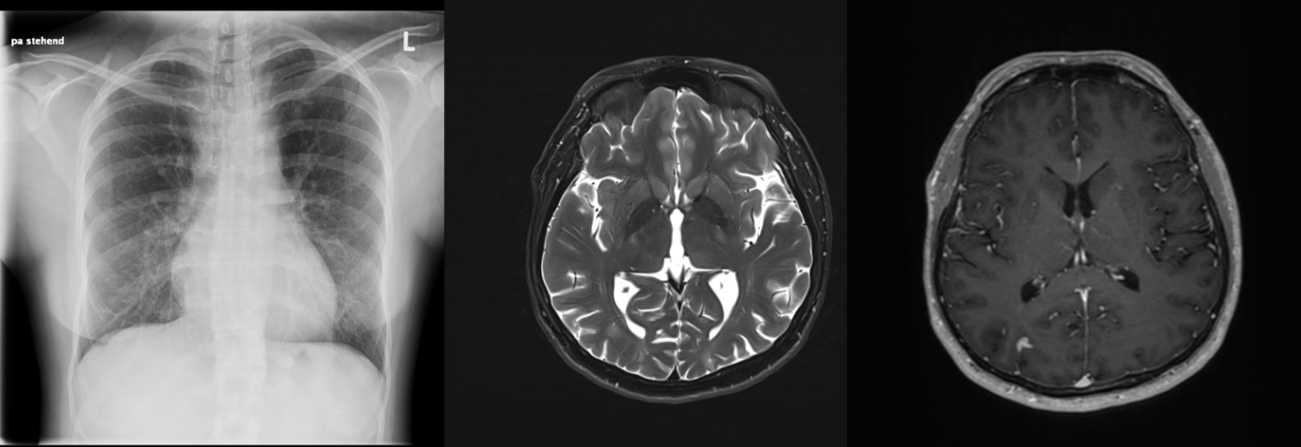

The chest X-ray and computed tomography scans showed disseminated patchy consolidation of the entire lung with a miliary pattern.

The cMRI showed intracranially-disseminated, contrast-enhancing lesions; some with extensive perifocal oedema and diffusion restrictions. An accentuated leptomeningeal contrast enhancement in the occiput and in the central sulcus on both sides were also found.